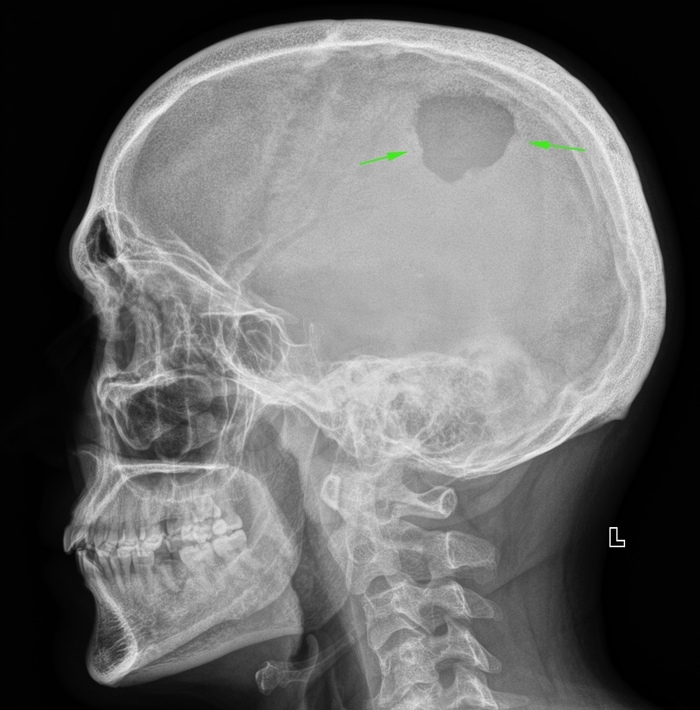

Случай 3. Трепанация черепа

Мужчина, 36 лет. В состояние алкогольного опьянения попал под поезд. Множественные переломы, ампутация правой нижней конечности (середина голени), оскольчатый перелом левой теменной кости. Вот эти осколки как раз и убрали во время трепанации черепа, а мы смотрели размер костного дефекта (3,5х2,7 см).